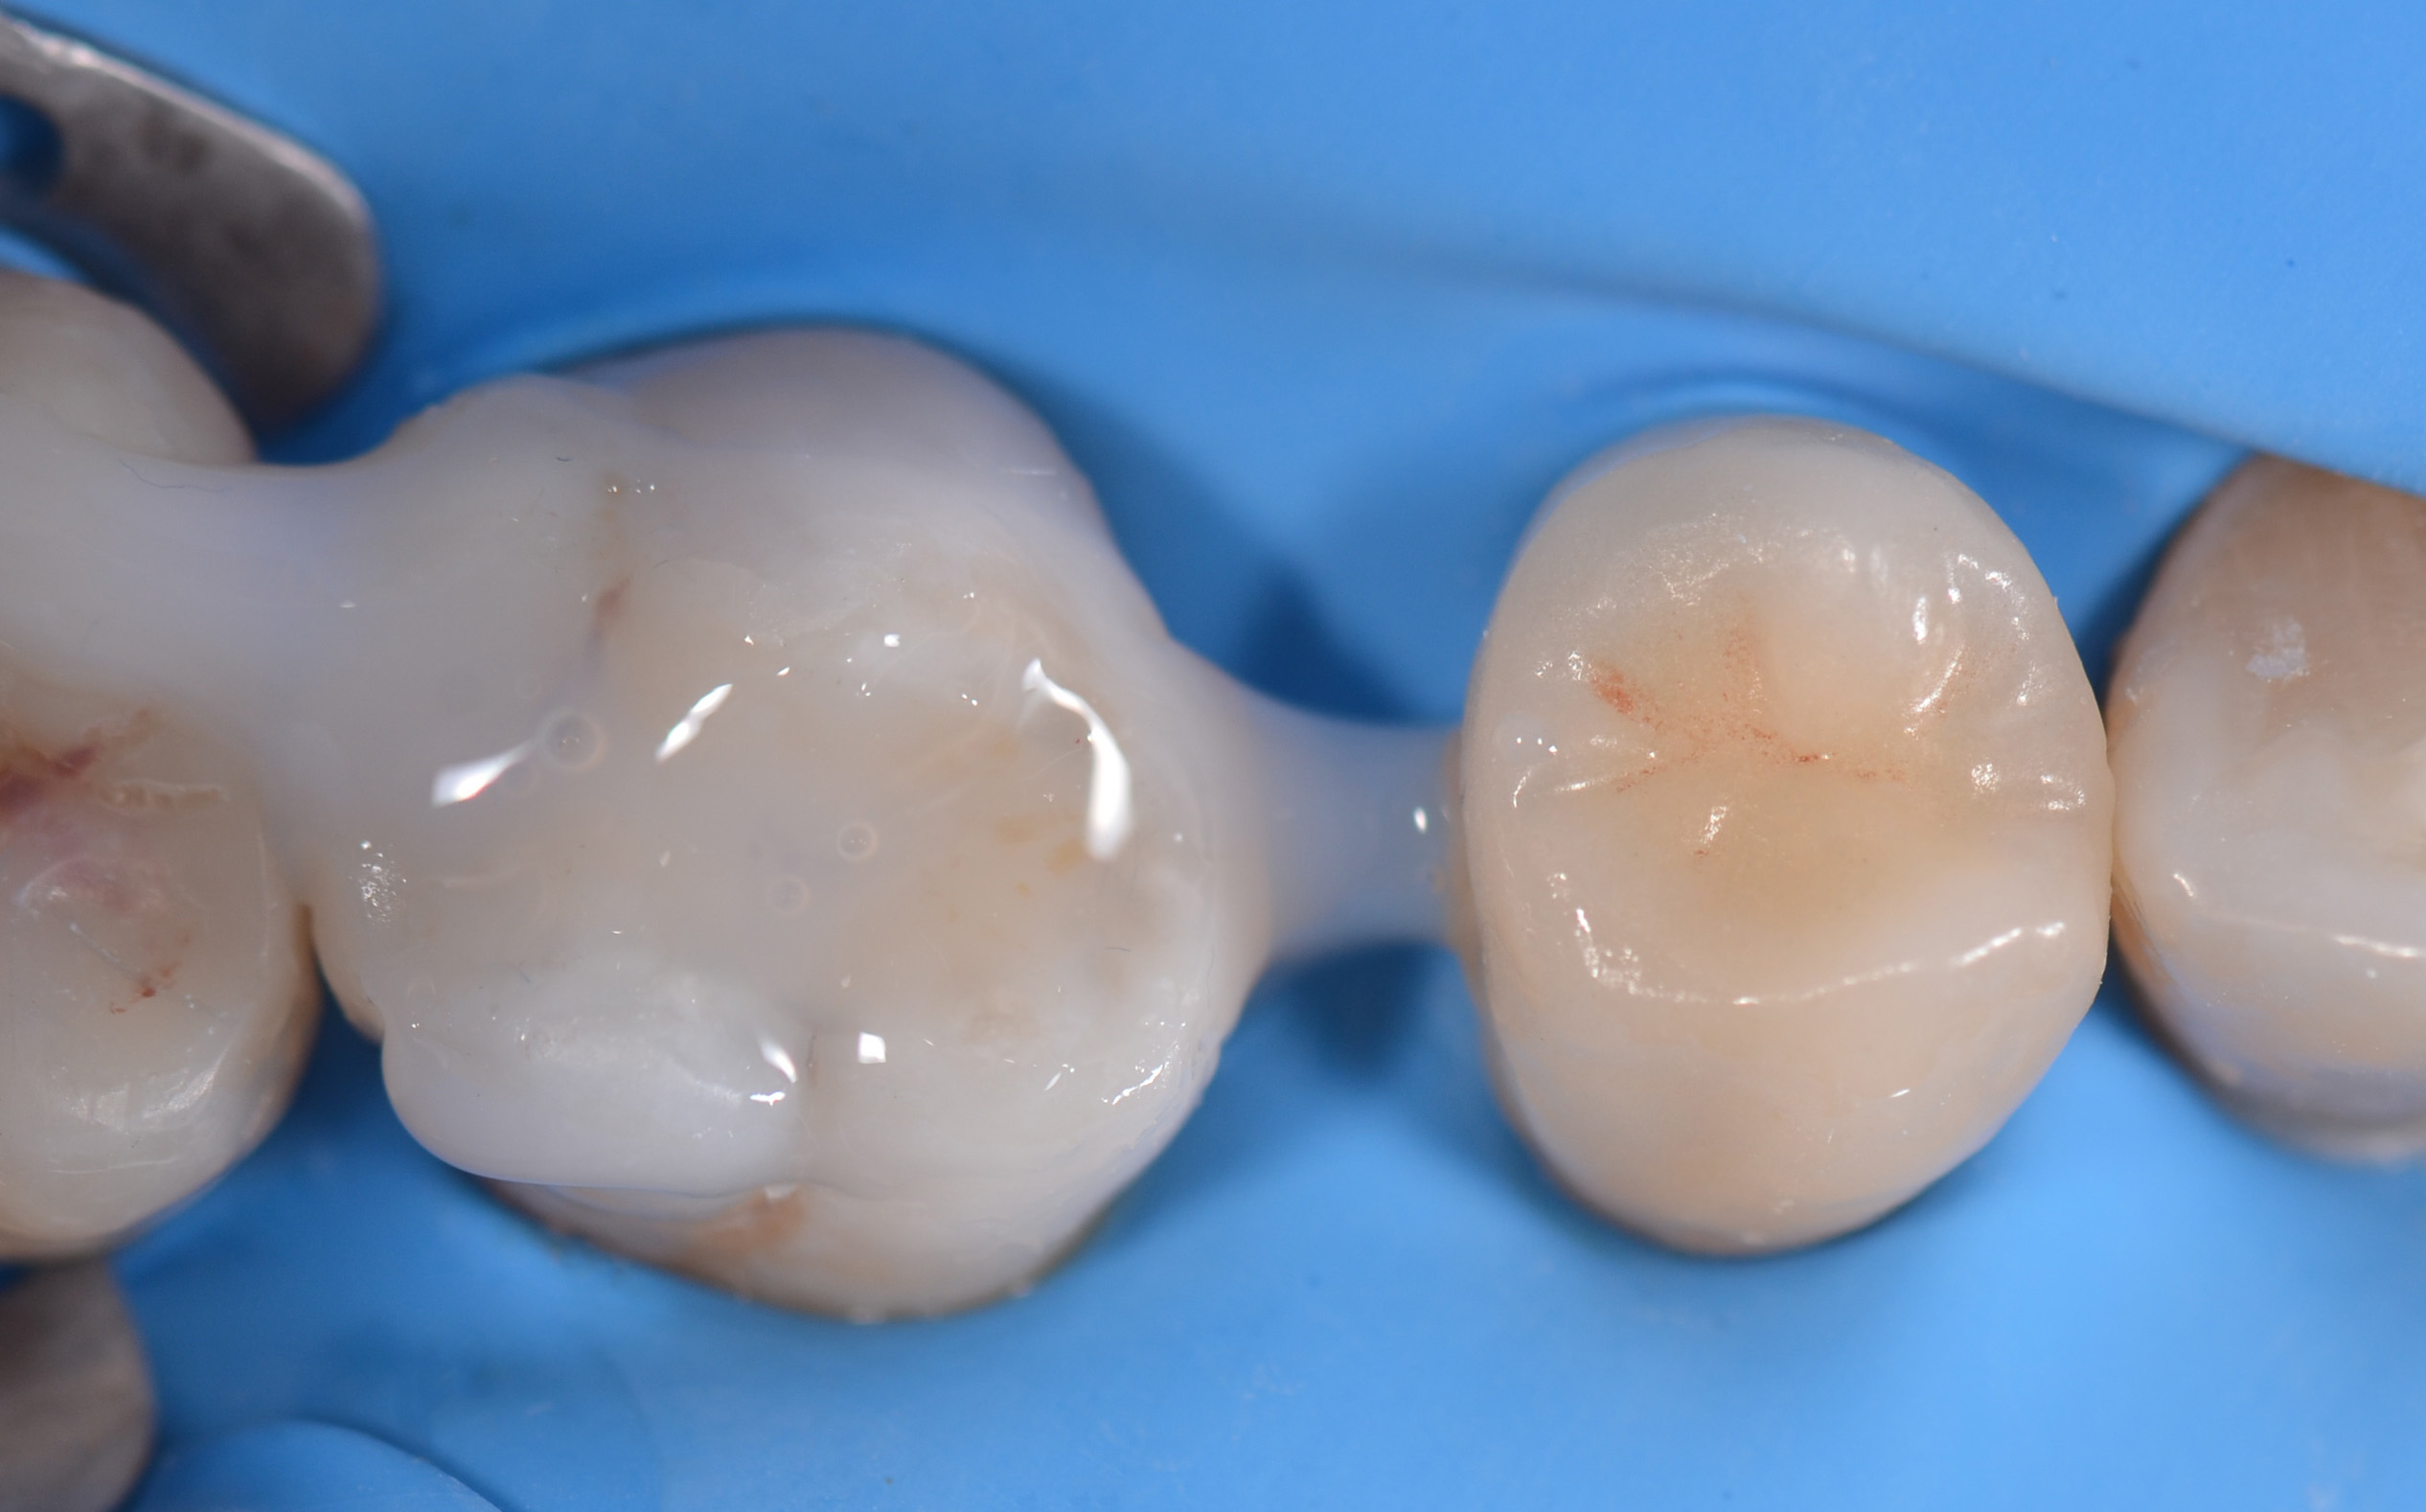

Contemporaneamente, si esegue l’isolamento del campo operatorio mediante diga in gomma, stabilizzata con uncino n. 2, e si effettua la prova del restauro in situ (19, 20).

L’onlay viene cementato utilizzando un composito universale a polimerizzazione duale, applicato sia sulla cavità che sulla superficie interna del restauro precedentemente condizionata.

Il restauro viene inserito con cautela. Nella fase iniziale si utilizza un otturatore a pallina (Figura 13) per esercitare una compressione intermittente lungo il solco principale, facilitando la fuoriuscita di eventuali bolle d’aria e del cemento in eccesso.

Segue una compressione continua con lo stesso strumento, per stabilizzare il restauro in posizione.

Infine, si esegue la fotopolimerizzazione finale su tutte le superfici esposte del cemento, in cicli di 20 secondi ciascuno (21) (Figura 15).

Rifinitura e lucidatura dei restauri

Dopo la rimozione della diga di gomma, per le zone di contatto si procede a rifiniture interprossimali con strisce abrasive. Concluso il controllo occlusale, per il molaggio selettivo dei precontatti si utilizza una fresa a pallina in carburo di tungsteno. Seguono quindi rifinitura e lucidatura con gommini abrasivi diamantati. Alcune superfici ruvide dell’overlay vengono rifinite e lucidate con l’ausilio di dischetti abrasivi a grana fine e di gommini. Con i dischi in feltro si passa alla lucidatura a specchio impiegando una pasta non abrasiva all’ossido di cerio. Dopo 15 giorni, si eseguono controllo radiografico e verifica del restauro eseguito (Figure 16-18). La Tabella 1 riassume il protocollo clinico utilizzato in questo case report.